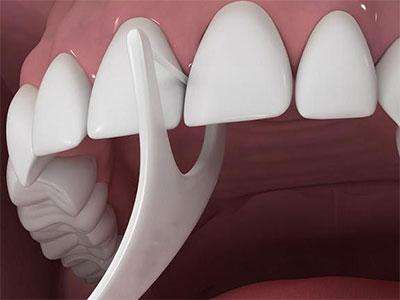

关于种植牙术后问题,柏德口腔医生建议大家使用软毛牙刷、单束牙刷、间隙刷等对种植体无损伤的,要使用低研磨的牙膏,可以有效去除菌斑,日常生活中可以搭配牙线使用,可以清除牙齿邻面菌斑,但不要频繁使用。